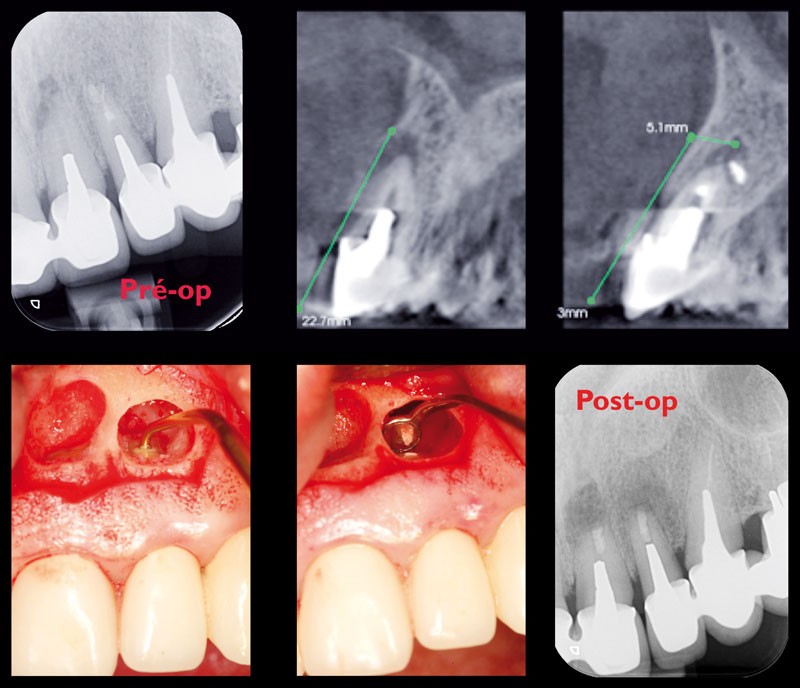

Élément indispensable du bilan préopératoire, l’imagerie conventionnelle (panoramique dentaire et/ou incidences intra-orales) reste suffisante lorsque la dimension vestibulo-linguale n’est pas nécessaire au diagnostic ou à la thérapeutique. Mais, pour s’affranchir des superpositions anatomiques inhérentes à la radiologie 2D, le chirurgien oral devra se tourner vers la modalité Cone Beam CT. La topographie du canal mandibulaire, l’analyse de la morphologie et de l’environnement des éléments inclus ainsi que l’évaluation volumique des kystes et tumeurs odontogènes bénignes des maxillaires, constituent les principales indications de l’imagerie de coupe dans le champ de la chirurgie orale hors implantologie.

Un examen Cone Beam CT est indiqué en complément des incidences conventionnelles de première intention, lorsqu’une exploration radiologique 3D est contributive au diagnostic, améliore la prise en charge ou est susceptible d’évaluer plus finement, voire de réduire, les risques chirurgicaux.

La réalisation d’une radiographie préopératoire est la règle avant tout geste chirurgical. Ainsi, une extraction, aussi simple soit-elle, doit systématiquement être précédée d’une imagerie 2D assurant une visualisation suffisante de l’ensemble de la dent et de son péri-apex. De même, l’exploration radiologique des dents de sagesse symptomatiques est évidente non seulement pour confirmer l’étiologie, mais également pour déterminer le traitement. En outre, l’absence d’une dent de sagesse sur l’arcade confrontée à l’interrogatoire médical justifie une exploration radiologique « de dépistage » recherchant une inclusion susceptible d’être associée à un processus kystique ou tumoral odontogénique d’évolution lente et asymptomatique (en particulier kystes dentigère/péri-coronaire…